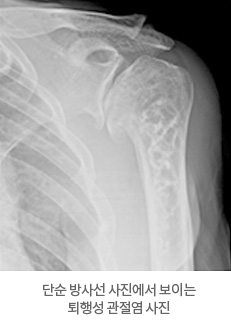

동통과 운동제한을 가진 환제에서 엑스레이 소견을 보면 알 수 있습니다.

엑스레이에서는 관절 간격이 줄어들고 골극이라는 비정상 뼈 만들어져 있으며 관절면이 불규칙하고 딱딱하게 경화된 특징을 보입니다. CT를 통해 관절면 변형 및 관절와 골결손을 정확하게 파악할 수 있기도 합니다.

단순 방사선 사진에서 보이는 퇴행성 관절염 사진